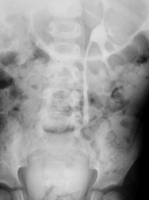

Histologisch sind das Granulationsgewebe bzw. die Granulome massenhaft von Schaumzellen (Makrophagen) durchsetzt. Als Erreger kommen gramnegative Bakterien wie E. coli (50%), Proteus (40%) sowie Staph. aureus und Klebsiella in Frage. Prädisponierdend sind Harnabflussstörungen z.B. durch Urolithiasis (Abbildung 17a).

Die Abbildungen zeigen die "stumme" rechtsseitige Niere im AUR sowie die retrograde Sondierung der rechten Niere bei dem Dreijährigen (Abbildung 18).

Das Krankheitsbild entspricht einem komplizierten Harnwegsinfekt. Bei ausgedehntem Prozess ist die Niere funktionslos, im AUR "stumme" Niere (s. Abbildung oben).